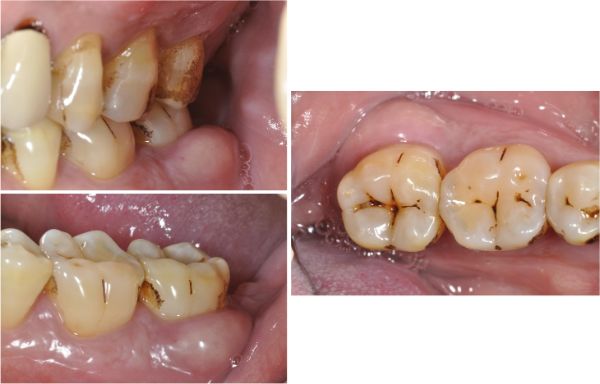

治療前,左下第二大臼齒牙周病

牙周破壞,牙齒動搖